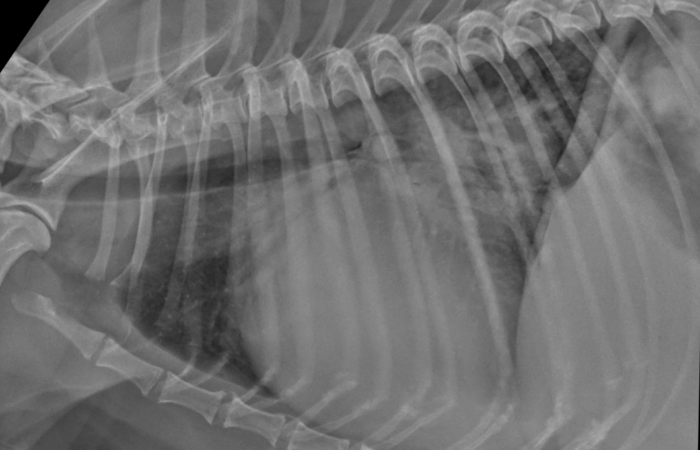

Our radiography reading sessions are a great way for our Specialists to bring new and interesting diagnostic imaging conundrums for discussion with our vtx community. In this session, the theme is thoracic imaging in small animals.